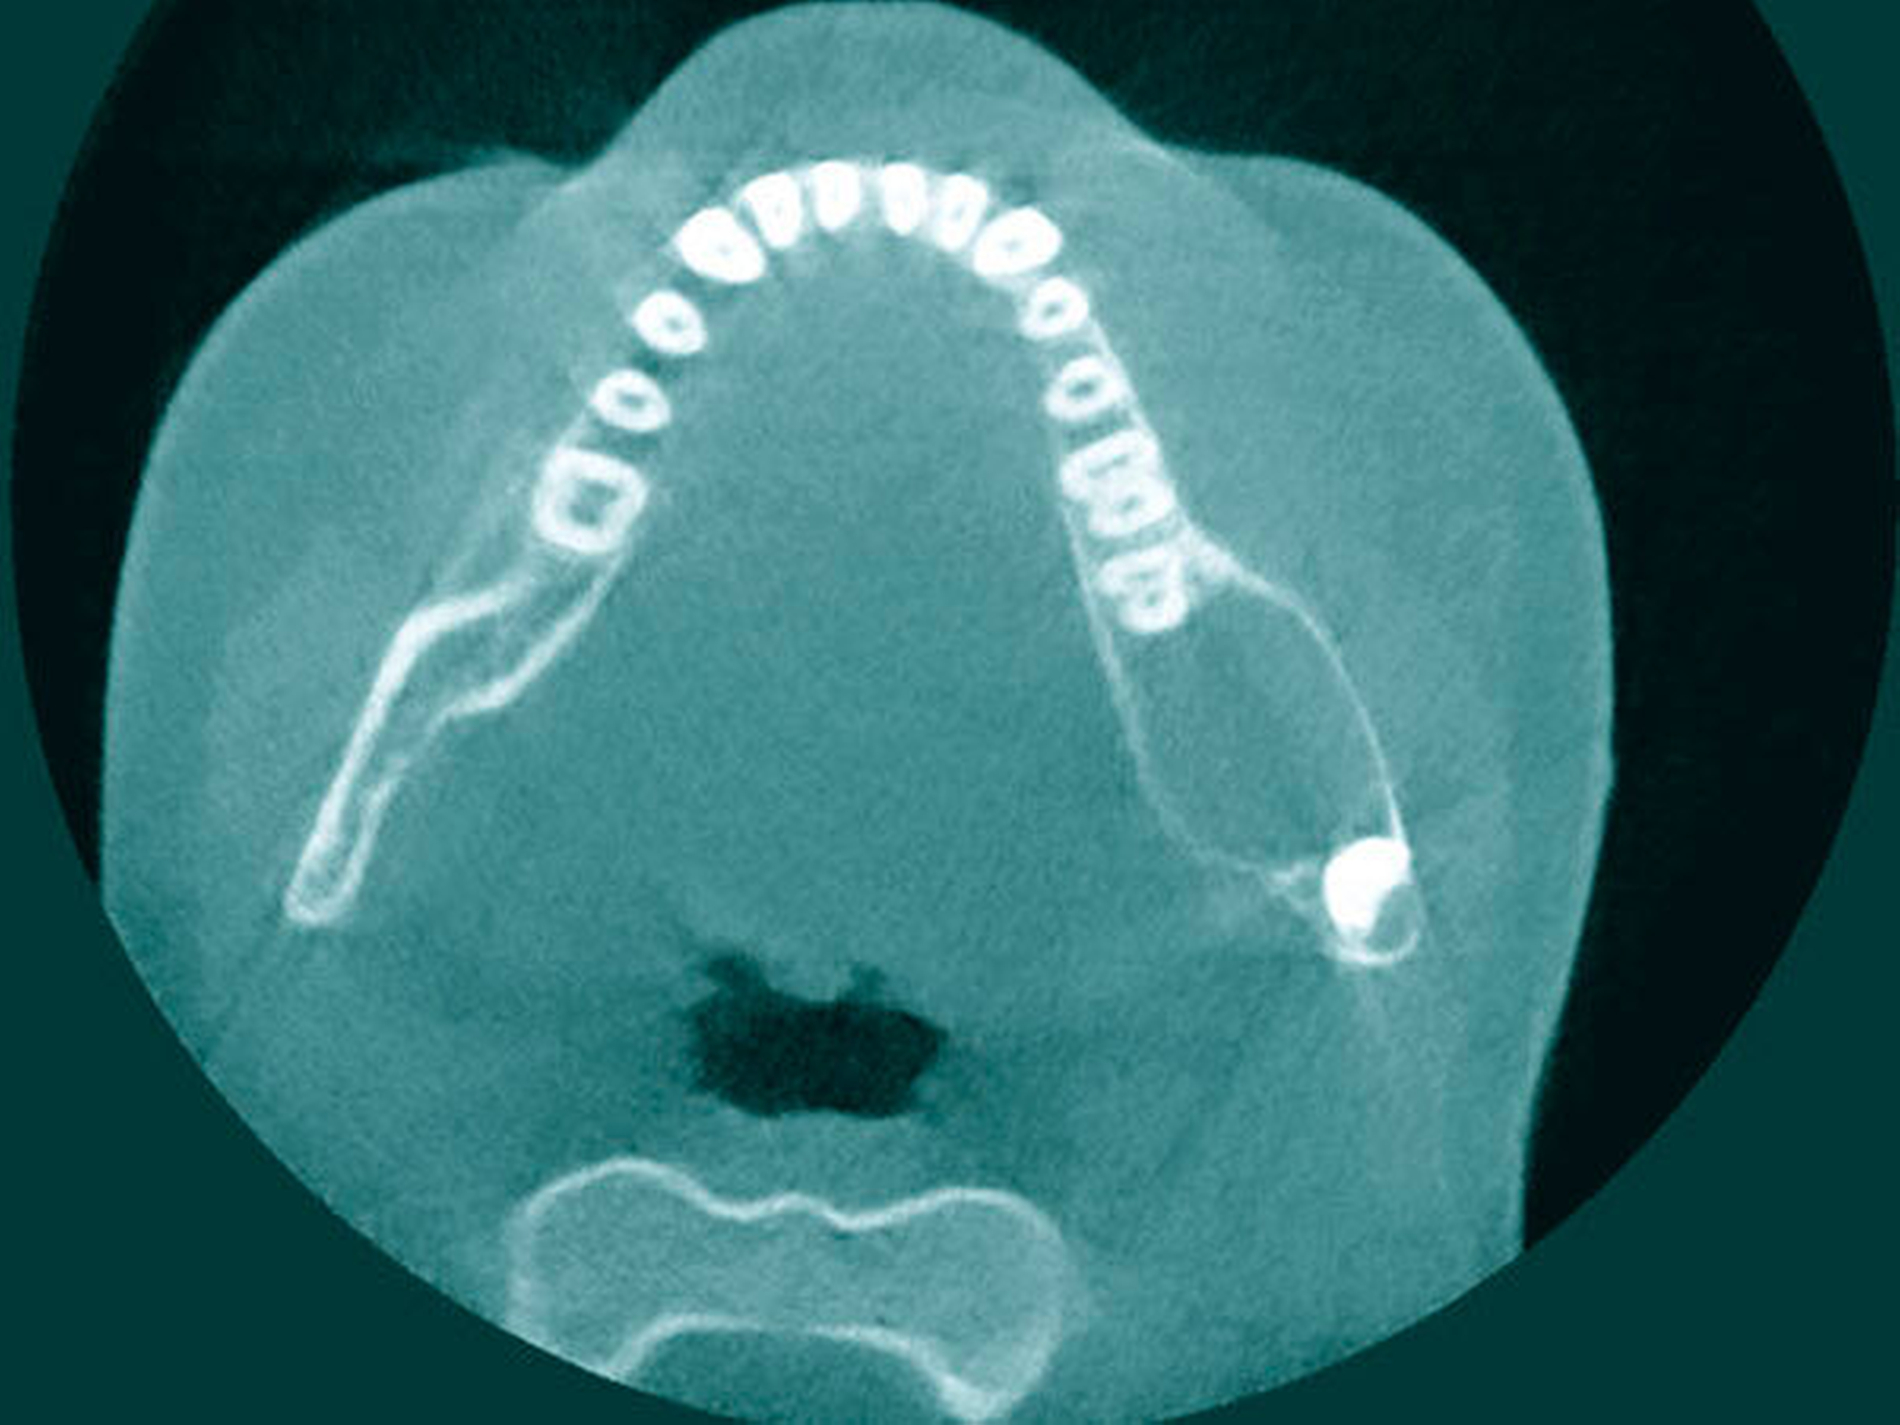

Eine 13-jährige Patientin kam in Begleitung ihrer Mutter mit einer seit drei Tagen progredienten Schwellung des linken Unterkiefers in unsere Klinik. Zuvor war durch den niedergelassenen Zahnarzt nach initialer Bildgebung bei Verdacht auf Vorliegen einer infizierten follikulären Zyste (Abbildung 1) eine enorale Inzision mit Einlage einer Drainage zur Entlastung durchgeführt worden.

Im Lokalbefund zeigte sich eine stark druckdolente perimandibuläre Schwellung des linken Unterkiefers (Abbildung 2), wobei die junge Patientin aufgrund der Schmerzen ihren Speichel nicht mehr schlucken wollte. Zur Feststellung der Ausdehnung und Abgrenzung gegenüber Nachbarstrukturen erfolgte die weiterführende 3-D-Diagnostik mittels DVT (Abbildung 3). Aufgrund der klinisch ausgeprägten Beschwerdesymptomatik sowie radiologisch nicht eindeutigem Bild (follikuläre Zyste ausgehend von Zahn 38 beziehungsweise odontogene Keratozyste) erfolgten eine Probeexzision der Zystenwand sowie eine Erweiterung der Drainage in Intubationsnarkose. Der bereits vorhandene Schnitt wurde auf regio 35–37 vestibulär ausgeweitet und der subperiostale Knochen dargestellt.